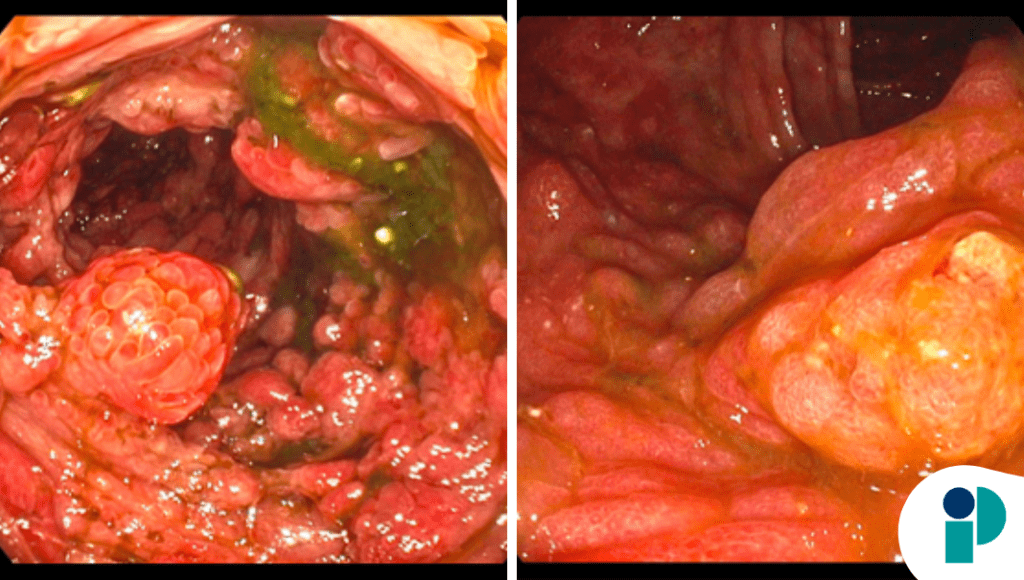

Aunque presentó una mejoría inicial con ganancia de peso, los síntomas digestivos persistieron y motivaron una reevaluación. Nuevos estudios evidenciaron poliposis gastrointestinal difusa con compromiso de estómago, duodeno y colon, sin hallazgos de malignidad en las biopsias.

La discusión multidisciplinaria permitió establecer el diagnóstico de síndrome de Cronkhite-Canada, una entidad caracterizada por poliposis gastrointestinal no hereditaria, síntomas digestivos crónicos y manifestaciones ectodérmicas.